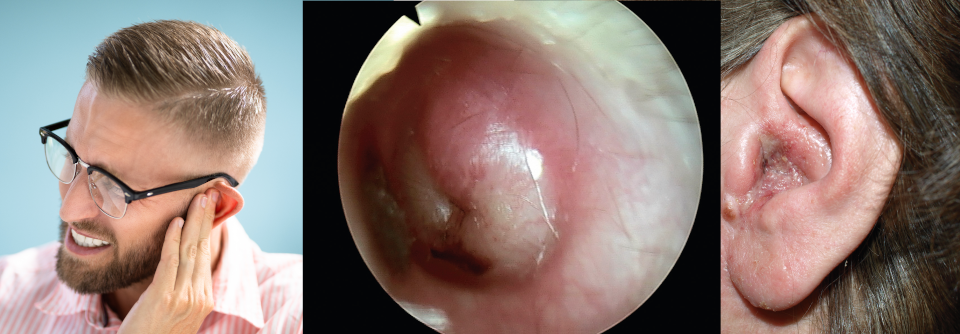

Bläschen deuten darauf hin, dass die Eustachi-Röhre wieder funktioniert. Bläschen deuten darauf hin, dass die Eustachi-Röhre wieder funktioniert. © Science Photo Library/PROFESSOR TONY WRIGHT, INSTITUTE OF LARYNGOLOGY & OTOLOGY

Die akute Otitis media betrifft vor allem Vorschulkinder, meist als Begleiterscheinung einer Infektion der oberen Atemwege. Die Diagnose erfolgt per Otoskopie, die Behandlung in erster Linie mit Analgetika. Antibiotika sind nur in bestimmten Situationen erforderlich.